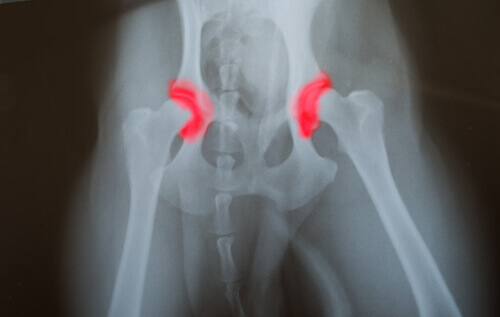

Stiamo parlando di una malattia ereditaria che passa di generazione in generazione. Interessa le ossa che formano le articolazioni, dell’anca o del gomito, che appaiono non posizionate o allineate correttamente.

Questa anomalia produce un fastidioso strofinamento e movimenti inappropriati. Il risultato è un’usura accelerata e costante che causa altri problemi dovuti al malfunzionamento dell’articolazione. Il problema di questa malattia silenziosa è che risulta difficile da riconoscere.